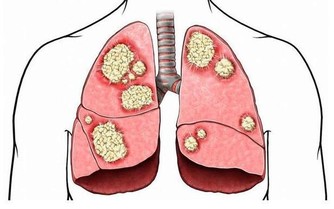

呼氣時,肌肉放輕鬆,此時橫膈膜將會比平常上升,可以進行深度呼吸,吐出停滯在肺底部的二氧化碳。